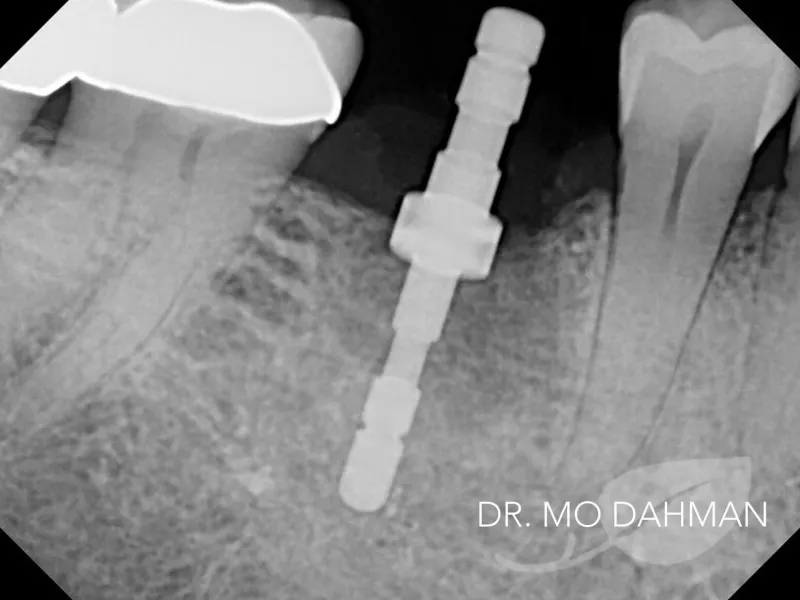

First, Dr. Dahman removed the problem tooth and bone was then grafted in it’s place. This procedure only took a single one hour appointment. Once complete the graft was left to heal for 3 months. After healing Dr. Dahman placed the new implant under the gum line. This procedure was completed in a short 45 minute appointment. Once complete the patient’s implant was allowed to heal as normal for an additional 3 months.

Once healed, a new tooth was made and placed on the implant in two easy 30 minute appointments.